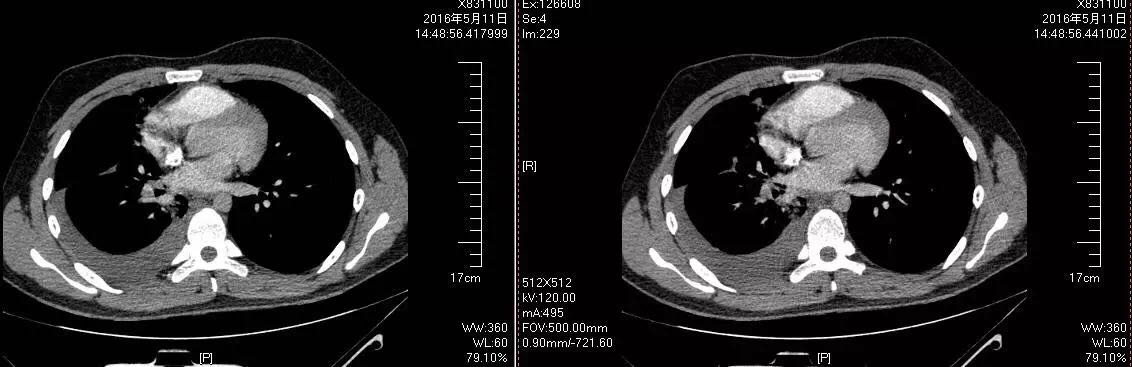

给病人进一步完善心脏超声未见明显异常,确诊低危组肺栓塞合并肺梗死,给予低分子肝素序贯华法林抗凝治疗,病人咯血停止,仍有低热、胸痛,再次给予胸腔穿刺排除感染,考虑吸收热,继续抗凝治疗后病人病情好转出院(见图4)。

图4